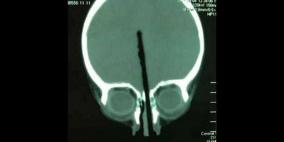

طفل صيني يتجنب الموت بعد اختراق عصاة الطعام دماغه عبر أنفه